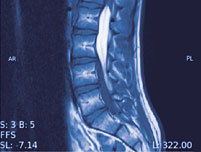

Abb. 1

In Höhe des 5. Lendenwirbels gelegenes Neurinom, welches den Raum innerhalb der Rückenmarkshaut vollständig ausfüllt.

In aller Regel (40%) bilden sich hier gutartige und nur langsam wachsende Tumore ohne eigene Ableger. Die sogenannten Meningeome gehen von der Rückenmarkshaut, die sogenannten Neurinome von einer Nervenwurzel aus. Die Meningeome befinden sich meist im Bereich der Brustwirbel und kommen gehäuft bei Frauen nach der Menopause vor. Die Neurinome (Abb. 1) gehen hingegen von den Nervenwurzeln selbst aus und können an jeder Stelle, teils sogar gleichzeitig an mehreren Stellen, vorkommen. Selten durchbrechen sie die Rückenmarkshaut und dehnen sich in den Wirbelkanal aus. Die Meningeome und die Neurinome sind gut begrenzt, üben aber aufgrund ihres Wachstums einen zunehmenden Druck auf die Nervenstrukturen aus. Sie können sich somit durch örtliche, häufig während der Nacht auftretende Schmerzen oder aber auch durch Lähmungen oder Ausfälle der Sensibilität bemerkbar machen. In seltenen Fällen können Tumore von anderen Strukturen innerhalb der Rückenmarkshaut ausgehen (Abb. 2).